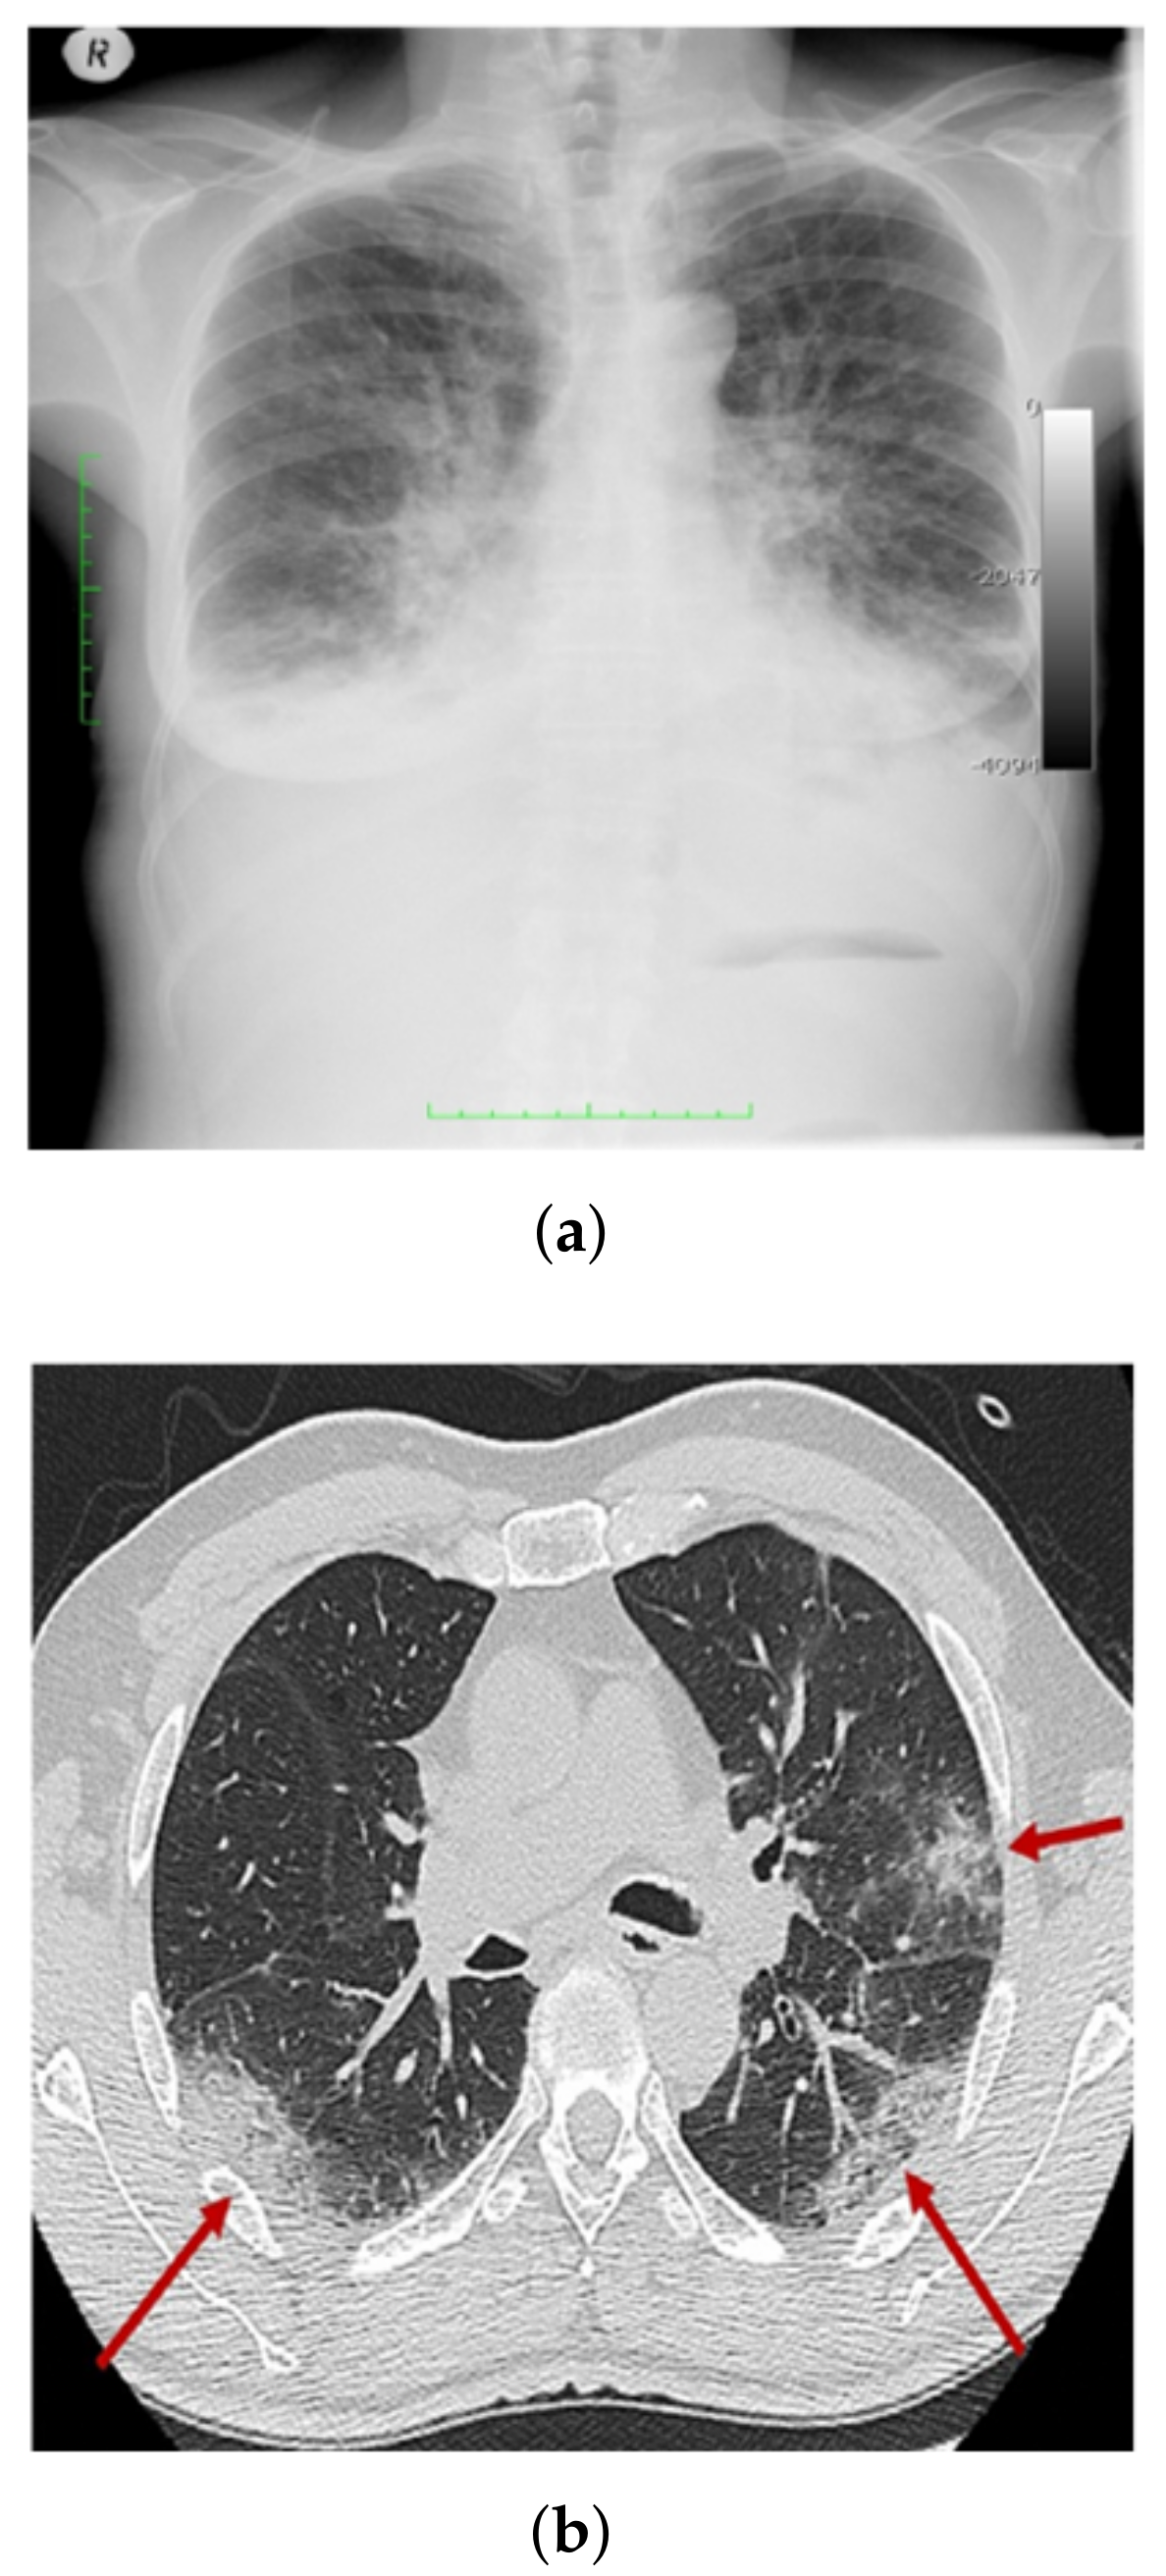

3.1. COV-PEN Image Datasets